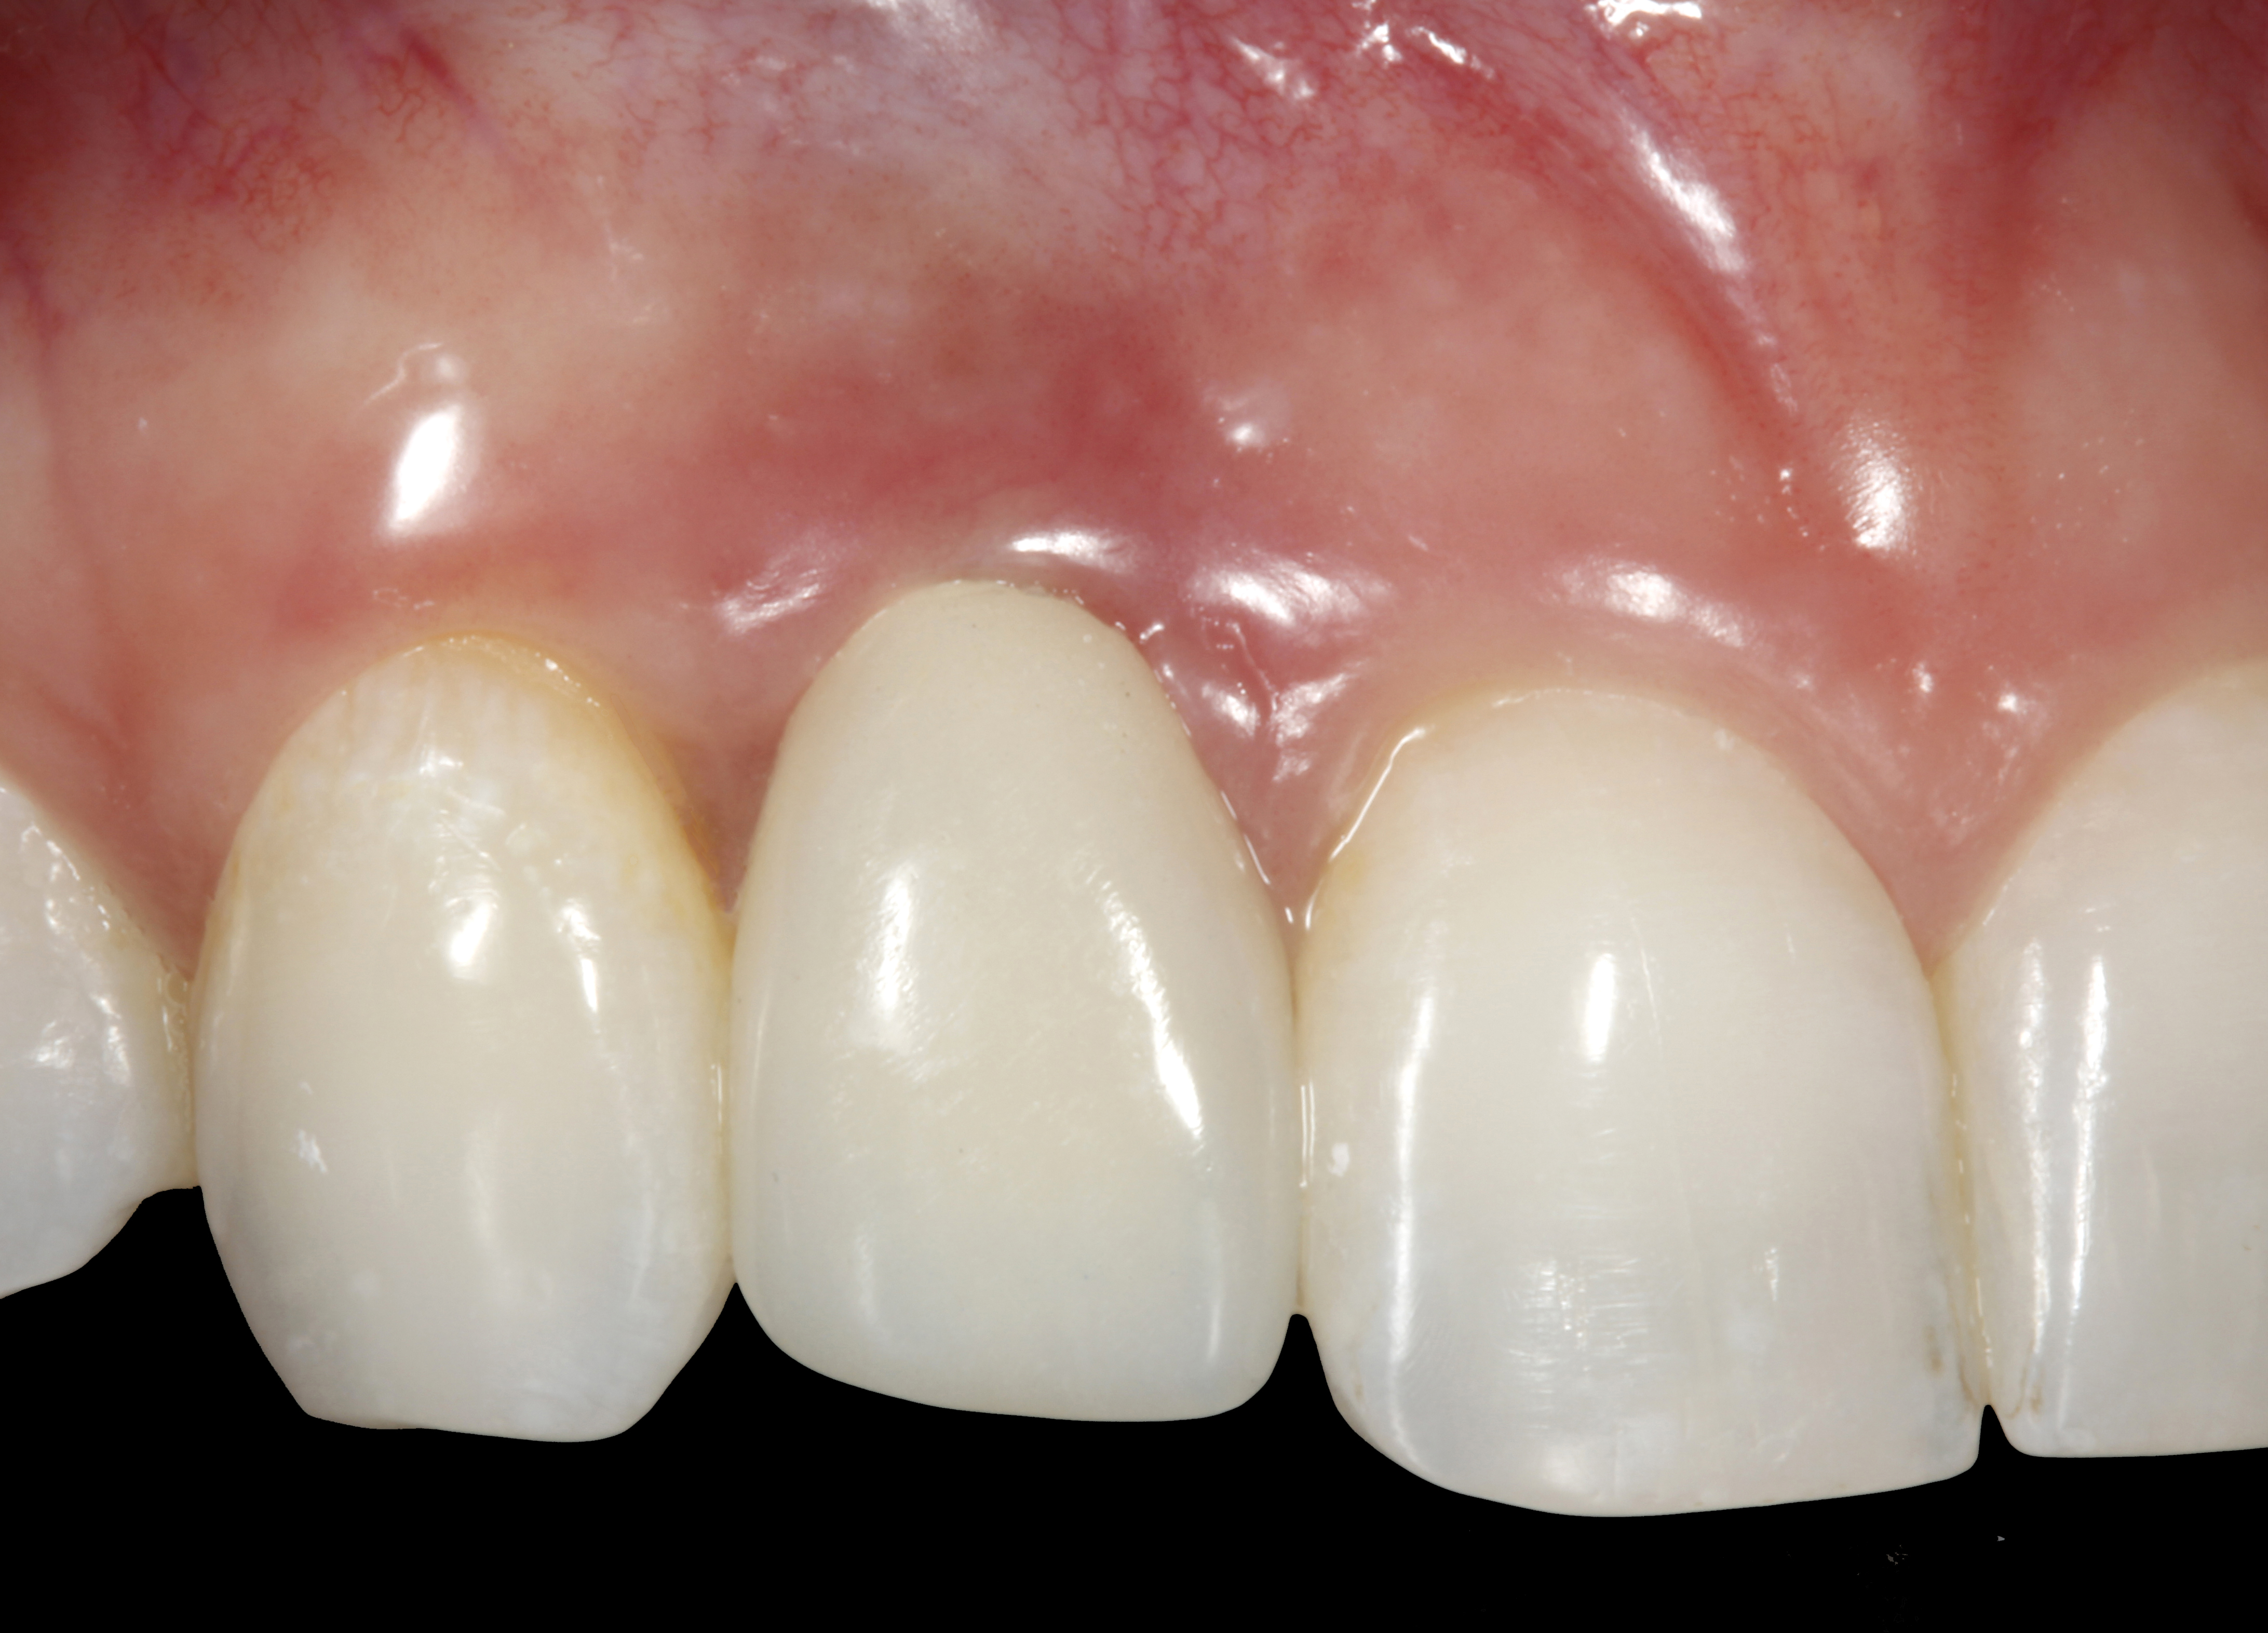

The crown and screw-retained custom abutment were removed, and a surgical cover screw was placed into the implant, thereby allowing spontaneous gingival augmentation in situ (Figure 33 and Figure 34). Note that the lingual aspect of the implant site was significantly more coronal than the labial aspect, which was positive because the defect would be limited to a facial–lingual defect. A fixed RBR bridge was cemented on the adjacent teeth and used as a tooth-supported transitional provisional restoration (Figure 35). A few weeks were allotted to let the soft tissue heal and migrate around the cover screw (Figure 36) to see if there would be complete coverage, thereby allowing a soft-tissue augmentation procedure to be performed with primary flap closure as in clinical scenario No. 2. The major obstacle in achieving a positive tissue response was that the implant depth was also deficient because the implant–abutment connection was at the level of the free gingival margin. It was decided that the best treatment option would be to remove the implant. A high-powered reverse-torque device (Fixture Remover Kit, NeoBiotech, www.neobiotechus.com) was used to remove the implant atraumatically (Figure 38 through Figure 41). The implant socket was allowed to heal for several months not unlike an extracted tooth (Figure 42). A new implant was placed in a better position from both a restorative and esthetic perspective (Figure 43), and after a few months of healing, a new crown was made (Figure 44). A satisfactory functional and esthetic result was achieved (Figure 45 and Figure 46) without employing pink porcelain.

Fig 45. The definitive crown tooth No. 26 seated in place and provisionally cemented. The recession defect was eliminated with the removal and replacement of a new implant in the proper position.

Figure 45